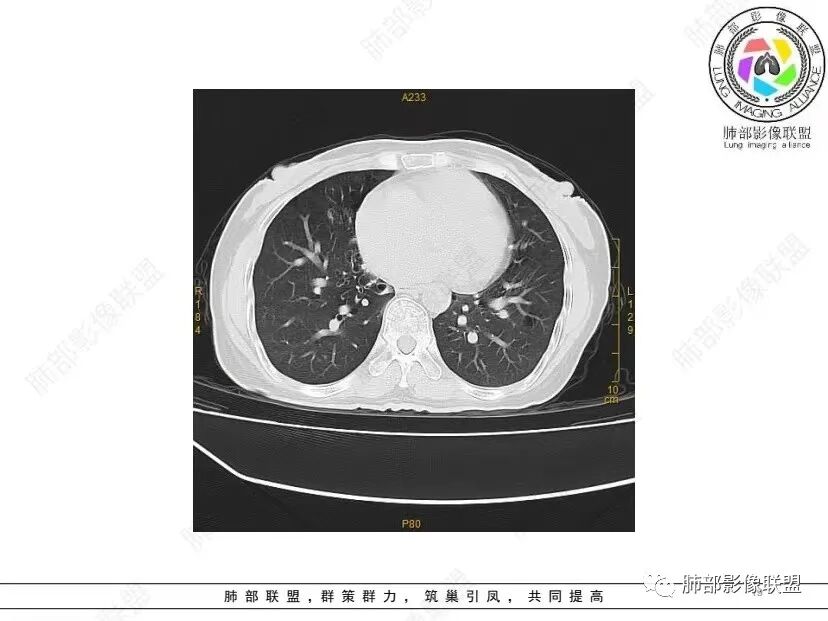

中年女性,否认肿瘤病史,双肺多发气囊,中下肺相对多发,考虑LIP,鉴别BHD综合征。

秦化君: 晨读 双肺不均匀散在多发囊状影,大小不等,部分囊形态欠规整,壁薄均匀,部分囊胸膜下平行。双肺少许斑片状磨玻璃影,边缘模糊。考虑BHD综合征。鉴别PCP,LIP。

红日初升: 中年女性,双肺多发气囊,背景干净,大小不一,下肺韧带旁较大,考虑BHD,鉴别LIP、LAM

玫: 晨读:女,49岁,双肺散在多发囊性病灶影,薄壁,部分层面病灶形态欠规整,右肺下叶少许磨玻璃影,边缘模糊,考虑LIP,鉴别BHD。

宇宙: 中年女性,两肺多发大小不等薄壁囊状影,两肺纵膈胸膜下分布明显,考虑BHD,鉴别LAM

放射线 (王秀仙): 双肺多发囊状影,大小不等,部分囊壁呈磨玻璃样,另双肺见斑片状磨玻璃影,边缘模糊。女性,考虑LIP,鉴别BHD

段建民: 双肺多发囊状影,多成圆形或三角形,囊壁薄且均匀,正常肺野内透过度尚可。双肺多发囊状影的鉴别,中心肺气肿,间隔旁肺气肿,PJP,支气管扩张,囊肿,支气管肺发育异常;LAM LIP PLCH BHD;囊腔腺癌,转移瘤,血播金葡菌……

本病例首先考虑BHD。

良孑: 两肺多发含气囊腔,大小不等,囊周见血管伴行,首选BHD,建议查双肾情况,鉴别Lam

这个病例目前影像特点,多囊,囊主要位于下肺,胸膜下及小叶核心为主

伴随少许索条,而且这些病灶与囊不一定有相关性

囊的分布,PLCH基本可以排除

囊壁薄且均匀,光滑,形态规则,基本除外恶性

单纯囊,无斑片及其他实性病灶,感染不支持,可能的是:LAM、BHD、LIP

从囊的分布、大小,BHD可能性可能大一些,但是LIP、LAM都可以这样表现,具体诊断应该是这三种之一,影像缩小到这里我觉得就差不多了,结合临床考虑就行,不支持靠影像强下结论。

临床诊断BHD综合征需要满足一个主要或两个次要标准。主要标准包括:1、皮肤上至少发现5个纤维滤泡瘤,至少1个组织学证实;2、致病的FLCN种系突变阳性。次要标准:1、多发肺囊肿,双侧基底部,有或无自发性气胸;2、肾癌,起病早(<50岁)或多灶性或双侧;3、 BHD综合征一级亲属。BHD主要影像表现特征:1、两肺内肺囊肿:80%以上的BHD患者会出现肺内囊肿,且倾向于基底部近胸膜下分布,特别是纵隔侧肺膜下,囊肿形状不规则、囊肿可大可小,肺内囊肿多毗邻肺下动脉或静脉近端,胸部CT上囊肿分布和特点对诊断有提示意义。2、继发自发性气胸:BHD患者发生气胸风险是正常人的5倍,BHD患者的气胸发生率约为1/4,气胸复发率则高达59%。3、肾肿瘤:(常为双侧性、倾向于嫌色细胞组织学亚型)4、皮肤表现:(为面、颈部纤维性毛囊瘤、毛盘瘤)